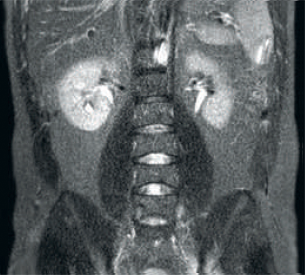

Resultado: resolución de imagen y SNR mejoradas

Resultado: imágenes ruidosas que usan parámetros de exploración idénticos

Mayor consistencia y mejor calidad de imagen La tecnología de recepción de RF dStream digitaliza la señal del resonador magnético directamente en la bobina de radiofrecuencia, lo que resulta en un aumento de hasta un 40 % más de la SNR* en todo el volumen de la imagen. Flujo de trabajo simplificado y rendimiento mejorado La bobina posterior integrada en la mesa elimina el manejo de la bobina en el 60 % de los exámenes. Las ligeras bobinas anteriores conformadas y las conexiones de bobina de un solo cable y de una sola mano contribuyen a la facilidad operativa.